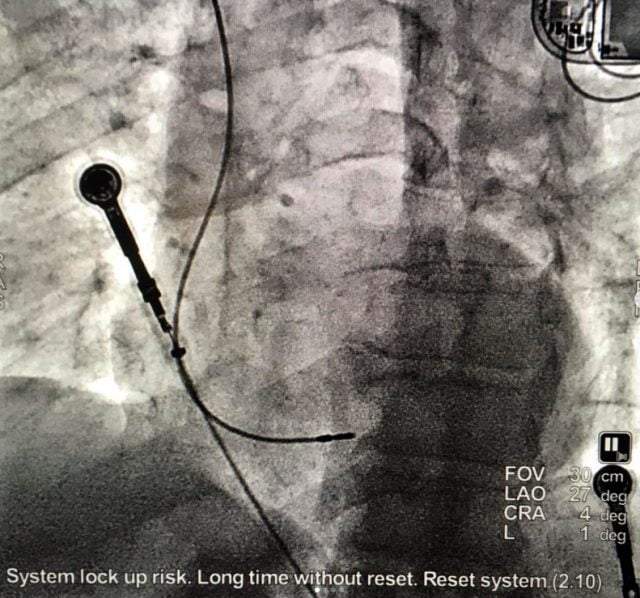

LBB pacing